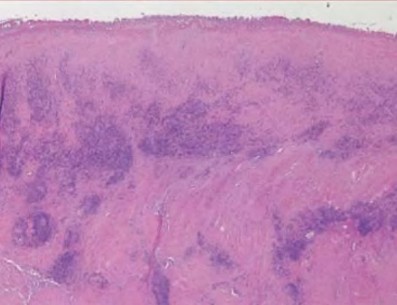

A 72-year-old female presents with progressive left thigh and knee pain for the last year. 5 years ago she sustained a femoral neck fracture treated with the implant seen in Figures A-C (current radiographs). The thigh pain is worse with weight-bearing. C-reactive

protein and erythrocyte sedimentation levels are within defined limits. Which of the following is the most likely cause of her pain?